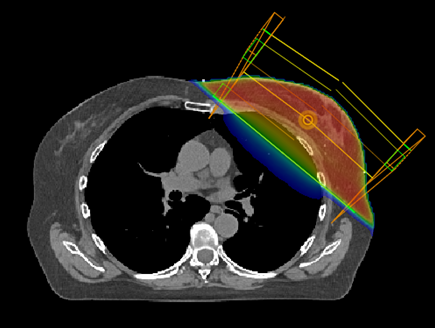

La radiothérapie conformationnelle se base sur l’imagerie en 3 dimensions de la tumeur ou le tissu à traiter et des organes environnants pour adapter (conformer) la forme des faisceaux au volume à traiter tout en épargnant au maximum les tissus sains avoisinants.

La radiothérapie conformationnelle avec modulation d’intensité (RCMI) et la radiothérapie avec modulation d’intensité Volumétrique par Arc Thérapie (VMAT)

Il s’agit d’une évolution de la radiothérapie conformationnelle tridimensionnelle qui permet non seulement d’adapter la forme du faisceau au volume cible mais aussi de faire varier l’intensité des rayons à l’intérieur du faisceau. Cette technique est particulièrement utile en cas de volume de forme complexe.

Dosimétrie

Durant cette étape, le dosimétriste va réaliser un plan de traitement sur un logiciel pour délivrer la dose prescrite à la tumeur tout en protégeant au maximum les tissus sains avoisinants. Ce traitement sera alors validé par votre médecin et un physicien médical.